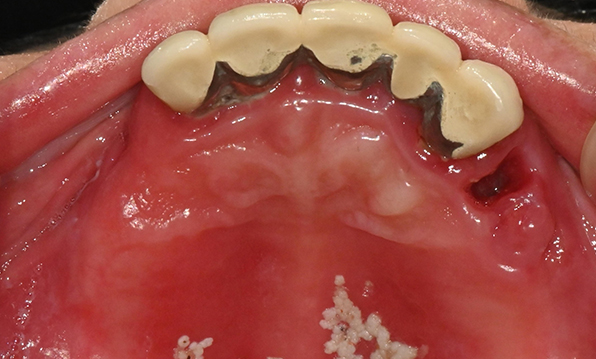

Before & After

| Before | After |